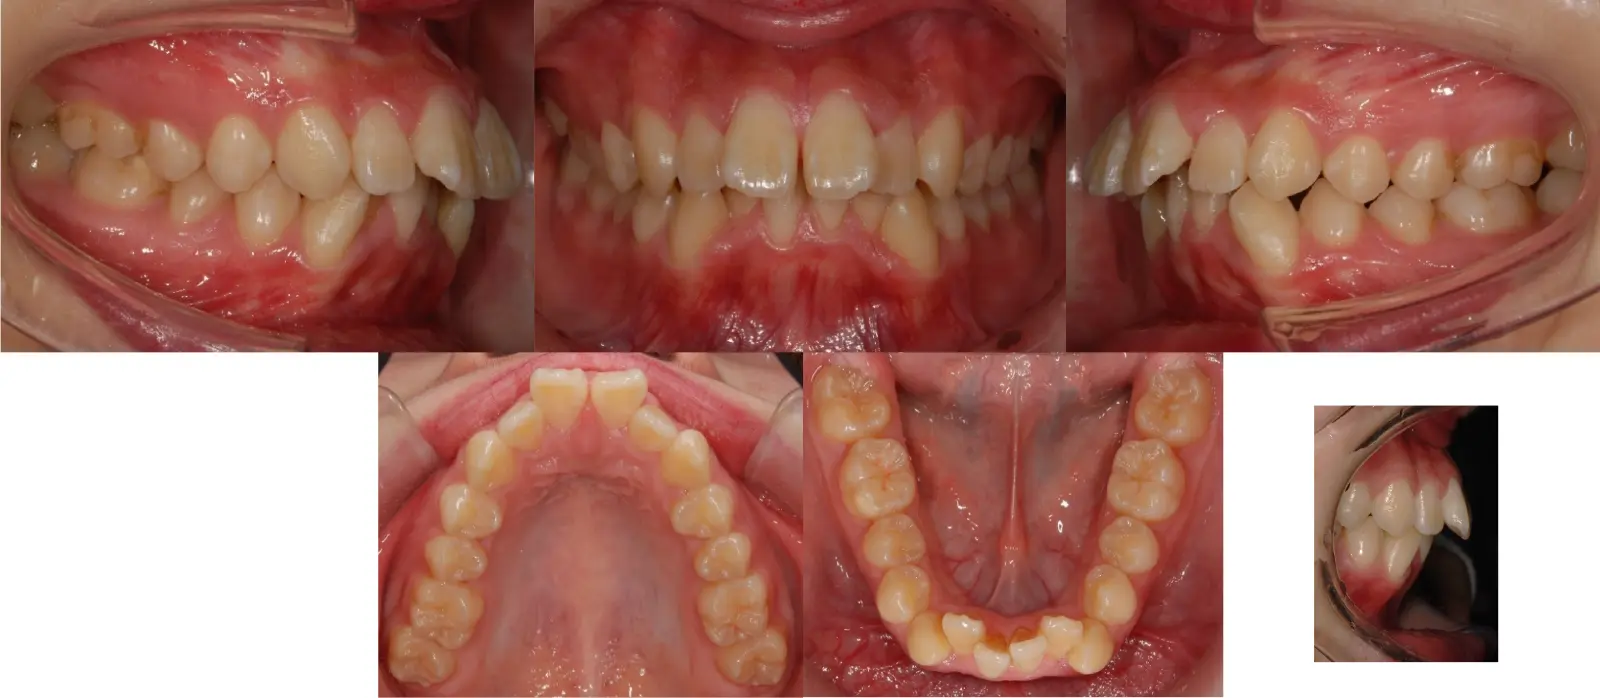

アングル1級叢生と過蓋咬合を伴う上顎前突症

- 主訴

口元の突出感と乱食歯

- 年齢

10代

- 治療期間

1年5ヶ月

- 治療回数

16回

- 治療に用いた主な装置

カスタムメイド型マルチブラケットタイプのデジタル矯正装置(インシグニア)

- 治療費

630,000円(税別)、調整料5,000円(税別)

- 抜歯部位

上下顎第一小臼歯 計4本